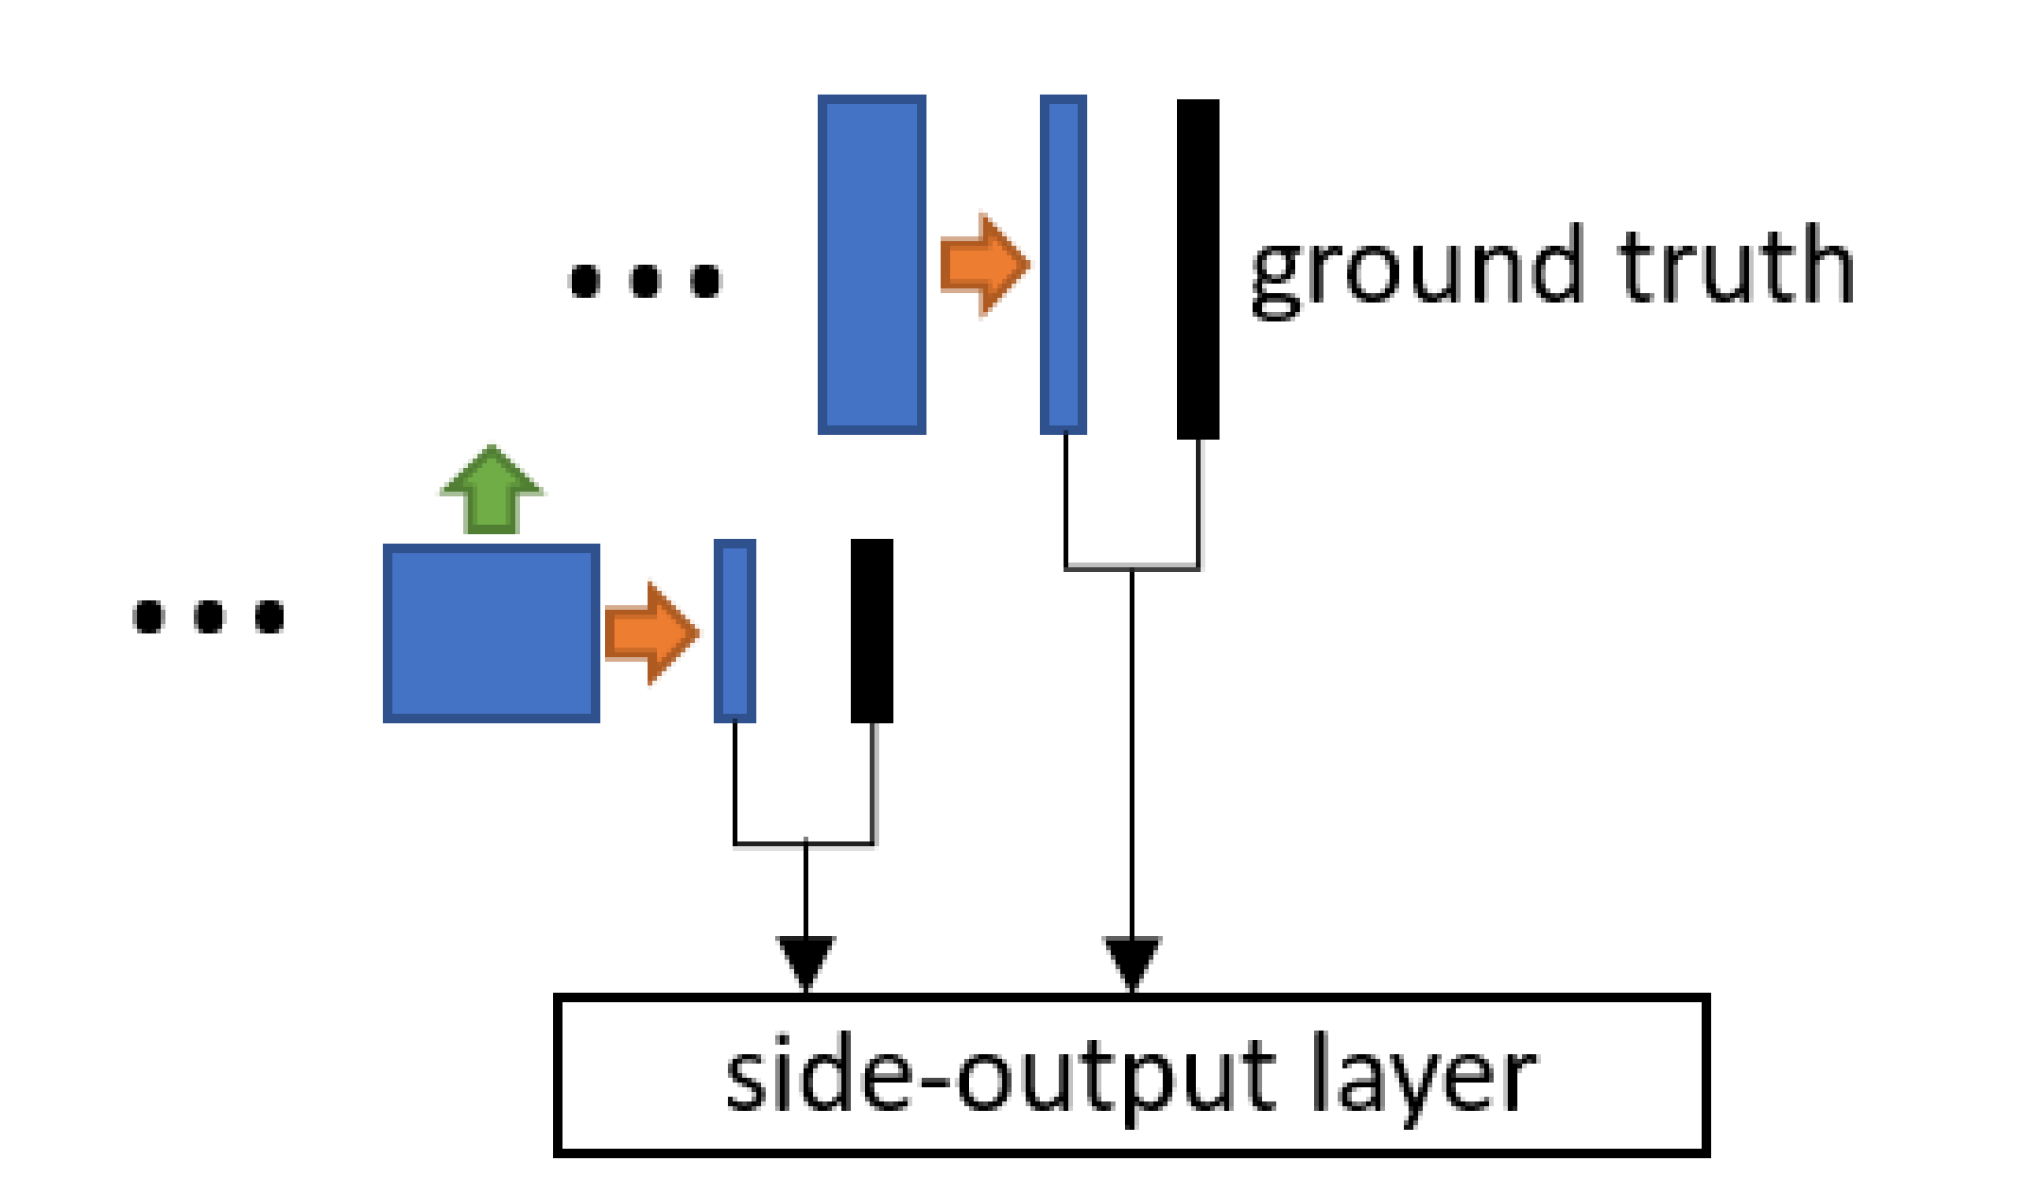

Three popular CNN blocks are utilized to modify the network structure. The dense block [8] is inserted in each level of the encoder path. The side-output layer [3] is employed to provide deep supervision in the decoder path. And the residual block [9] is integrated into the encoder, the bottleneck as well as the decoder. The block structures are illustrated in Fig. 1 (b-d).